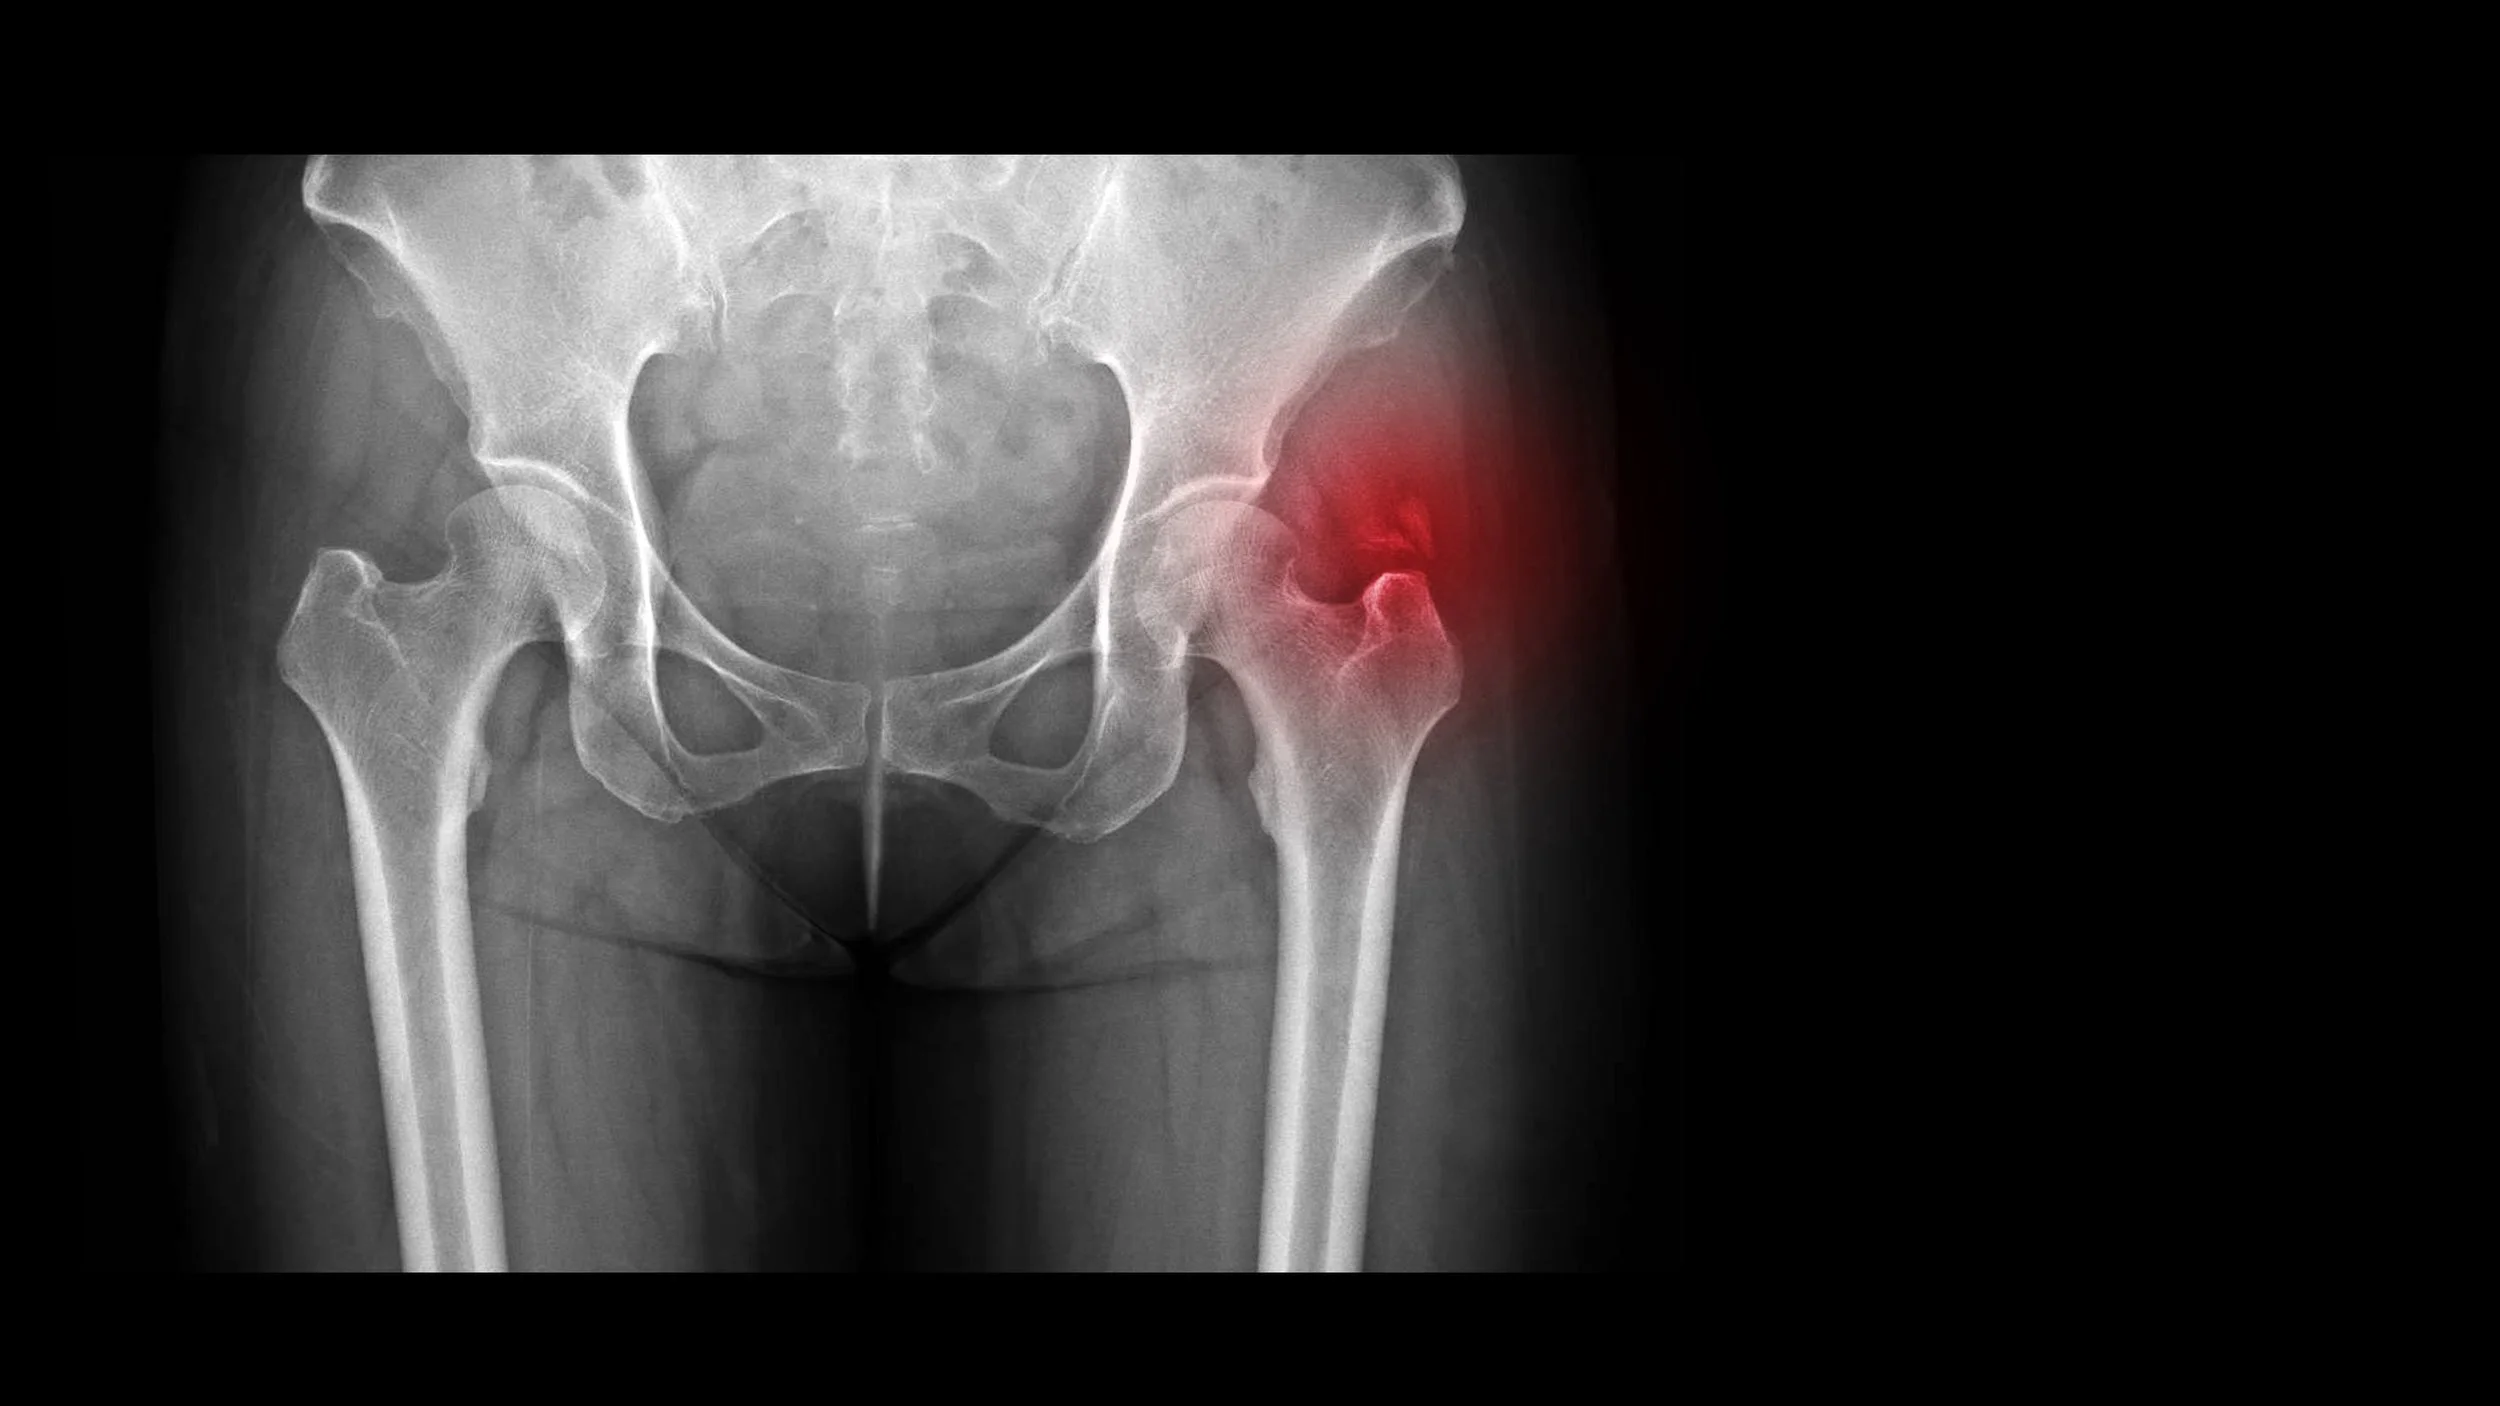

Gluteal Tendinopathy

Irritation or degeneration of the gluteal tendons near the hip, often presenting as outer hip pain, especially when lying or walking.